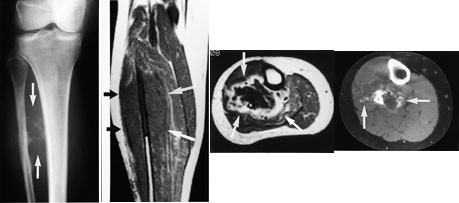

Ved osteogent sarkom og Ewings sarkom kan MR med snittplan i knokkelens lengdeakse nøyaktig fastslå øvre og nedre grense for tumorutbredelse i beinmargen (fig 5), påvise metastaser innenfor samme margrom og innvekst i ledd. Dette er forhold som har stor betydning for omfanget av kirurgiske inngrep. Som regel har tumor på diagnosetidspunktet brutt gjennom knokkelen og gitt opphav til en ekstraossøs komponent. Med snittplan perpendikulært på knokkelen kan MR vise om tumor affiserer kar og nerver, og hvilke muskler den ligger an mot eller infiltrerer. MR kan styre biopsitakingen til de områder av tumor hvor det er størst sannsynlighet for å finne representativt vev.

Konvensjonelle røntgenbilder er første trinn i utredningen av mistenkte bløtvevssvulster (12). De viser underliggende skjelettdeformitet, beinaffeksjon og bløtvevsforkalkninger. Forkalkninger kan ikke påvises med MR. MR er allikevel den beste metoden, fordi den i tillegg til å vise de anatomiske forhold også fremstiller væske, nekrose, blødning, fett og annet bløtvev (fig 6 – 8). Basert på vekstmønster og signalforhold kan vevsspesifikk diagnose stilles i 20 – 40 % av tilfellene. Det er oftest ikke mulig å angi om en bløtvevstumor er benign eller malign. Nekrose er den enkeltfaktor som sterkest peker i retning av malignitet. Andre faresignaler er stor tumor, uskarp avgrensning med omgivende ødem, heterogent signal og beinaffeksjon. Men høymaligne bløtvevssvulster kan være velavgrenset med en pseudokapsel.